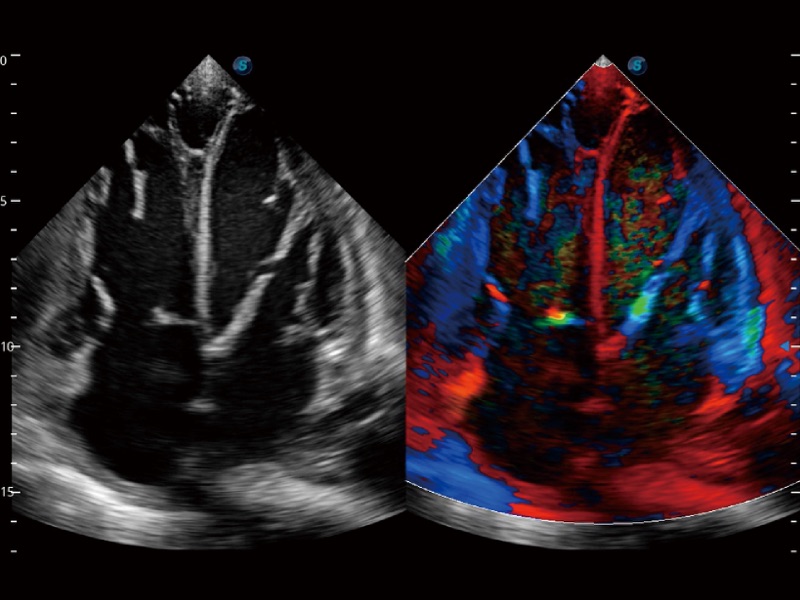

• SR Flow 高分辨率血流成像技术

高分辨率血流成像技术提高了对低速血流信号的检测能力。在提高空间分辨率的同时,也克服了血流外溢现象,为用户提供更加真实的血流动力学信息。

• 心血管应用